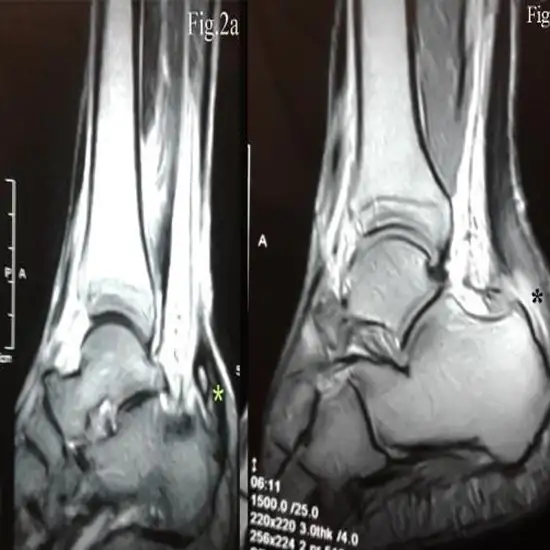

An MRI of the ankle joints shows the bones (tibia and fibula) and surrounding soft tissues (tendons, ligaments, muscles, blood vessels).

MRI pictures give surgeons a road map for making repairs to broken bones, torn ligaments, and ruptured tendons. The physician prescribes this test to diagnose any fractured bones in the ankle joint.